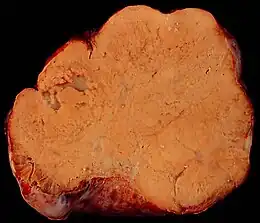

On appelle tumeurs de Krukenberg certaines tumeurs des ovaires. Bien qu’elles puissent sembler être des tumeurs primitives de l’ovaire, il s’agit toujours de métastases (c'est-à-dire de tumeurs secondaires), originaire le plus souvent d'une tumeur du système digestif, et notamment de l'estomac, ou parfois encore d'un cancer du sein. Souvent on trouve des tumeurs de Krukenberg dans les deux ovaires. Au microscope, elles sont caractérisées par l'apparition de cellules en bague à chaton qui sécrètent de la mucine ; quand on découvre la tumeur primitive, on y trouve les mêmes cellules en bague à chaton.